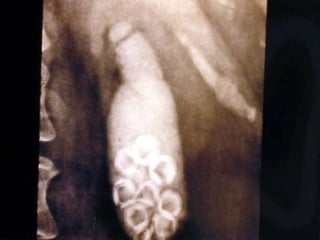

Cateter en el Cístico para Colangiografía

La Colangiografía

Una Ventana al Cístico

Cateter con Globo para dilatar al Cístico

Introducción de un cateter con Canastilla plegable

Cístico-Extracción de un cálculo

Coledociano

Extracción de un Cálculo Coledociano